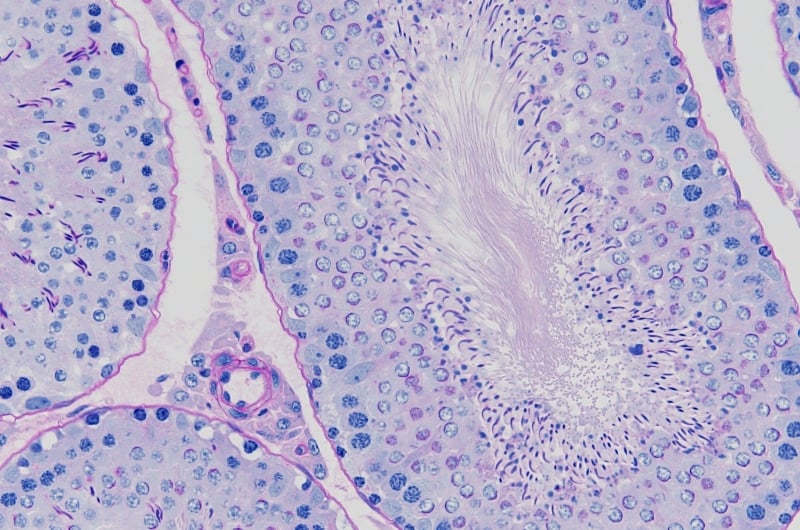

| 過ヨウ素酸シッフ (PAS)反応 →上皮系腺癌、真菌、赤痢アメーバ、など |

細胞内グリコーゲンや腎糸球体基底膜、尿細管基底膜、精巣のアクロソームが赤~赤紫に染まる

|

|---|---|